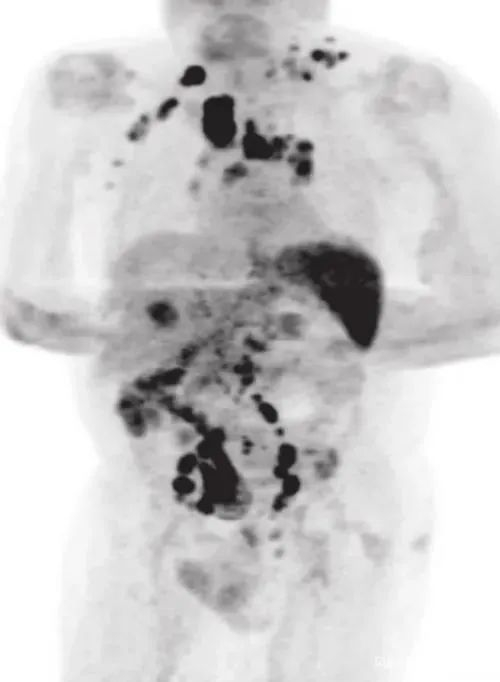

2020年年中,男子的身体突然之间暴瘦,并且全身淋巴结肿大,他赶紧到医院检查,结果确诊罹患经典型霍奇淋巴瘤,PET-CT扫描提示疾病分期为3期。

也就是说,男子此时是一名癌症晚期患者。CT照片也显示,癌细胞扩散到了他身体的各个地方。

四个月后,男子回医院复查。PET-CT扫描却提示,他体内的大部分肿瘤竟然神奇地都消失了。更为夸张的是,与肿瘤有关的生物指标直接下降了约9成。

反复检查后,医生们最终确认,男子的癌症痊愈了。而他的新冠检测也显示为阴性,男子体内的新冠病毒也消失了

发生在男子身上的状况让研究人员感到不可思议。目前,研究人员推测认为,有可能是新冠病毒触发了人体抗肿瘤的免疫反应,作用机制包含病原体特异性T细胞和肿瘤抗原的交叉反应,且染疫所产生的细胞活化了杀手细胞。说得直接一点,新冠感染激活了抗肿瘤的免疫反应,在杀灭病毒的同时,也杀死了癌细胞